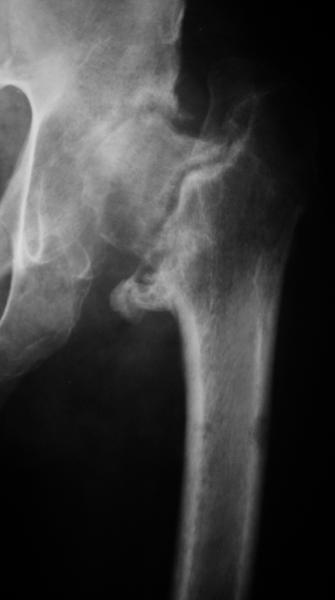

Насчет 8 см согласен с А.Н. Челноковым, это наверное ортопедическое за счет приводящей, сгибательной контрактуры и, возможно, колена. на ликвидацию укорочения у нас обычно уходит около 2-х нед. снимки в приложении, возможно не очень показательные, но других с ходу не нашел, завтра еще поищу.

А за счет чего такое укорочение? По снимку не видно соответствующего дефекта. Ну плюс приводящая контрактура - но все равно как-то уж больно много. Может, сделать снимки и таза обзорный с обоими проксимальными отделами бедра, и коенный суставов с приложенной линейкой какой?

Судя по снимку, максимум истинное укорочение около 4 см, что может быть коррегировано интраоперационно. Вопрос в другом: куда ставить ацетабулярный компонент в истинную или во вновь сформированную ( впадина диспластичная).

По рентгенограммам укорочение не более 4 см, остальное возможно за счет контрактуры. Опыта с низведением аппаратом Илизарова нет, но мы одномоментно такие укорочения корригировали вполне успешно (в год 5-10 именно таких и проходит). Лишние этапы пожалуй только будут способствовать инфекции. Доступ чаше применяем передне-наружный, а вот протез наверное поставили бы здесь на цементе - остеопороз выражен.

По уровню малых вертелов (с учетом рентгеновского увеличения) получается 5 см. Клинически ногу низвести путем тракции невозможно. Из движений - сгибание до 40*, остальные движения "символические".

Ортопедическое укорочение пострадавшей ноги может быть и 7, и 10 см. за счет контрактур в тазобедренном суставе, а вот истинное укорочение, судя по представленным рентгенограммам, вряд ли больше 4 см.

Больного прооперировали на прошлой неделе (цементный протез, цемент с гентамицином). Использовали задне-боковой доступ. В области перелома подвижности практически не было, так что тему сообщения уместно заменить на "неправильно сросшаяся шейка". И в головке, и во впадине

были значительные дегенеративные изменения, так что ни биполяр, ни остеосинтез тут неуместны (хотя это предлагали в ortopod'е). После релиза удлинили ногу на 3 см. Дальше удлинять побоялись из-за

натяжения седалищного нерва, хотя в принципе можно было бы еще 15-20 мм нарастить. По послеоперационной рентгенограмме анатомическое укорочение порядка 15 мм. Клинически при ходьбе - 4 см, но это за счет перекоса таза.

The patient underwent cemented THR on last week. Postero-lateral approach was used. There was only minimal motion at the fracture site and we had to cut the femoral head with oscillating saw. The femoral head was deformed with it's cartilage completely absent in some areas.

Acetabulum showed gross degenerative changes, especially in superior rim. So I think it was right choice not to do ORIF in this case. After some soft tissue release we've lengthened the leg up to 3 cm. Further lengthening was possible but we stopped at that moment due to tension of n. ischiadicus. Now patient walks with crutches. Leg length discrepancy is about 4 cm due to pelvic tilt (discrepancy on post-op x-ray is 15 mm).